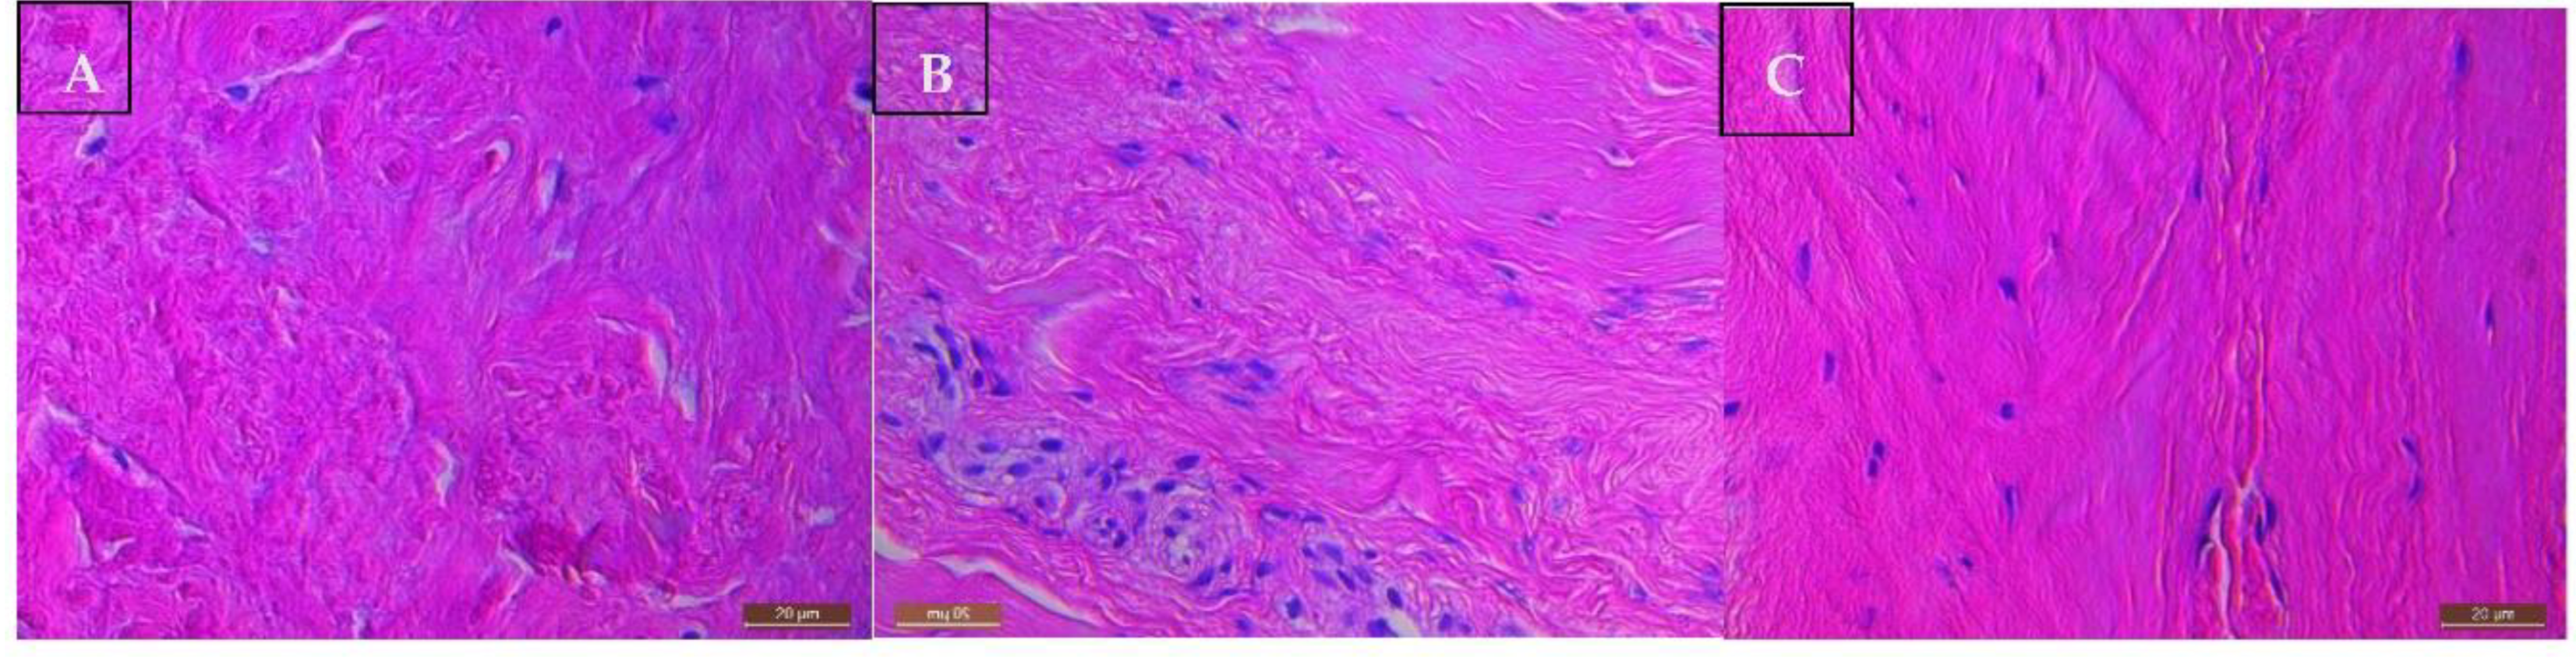

The supraspinatus tendon tissue of all patients with a rotator cuff tear showed Bonar grade 4 changes consistent with features of marked tendinosis (Figure 4A). Tenocytes had a rounded morphology. There was a loss of the normal dense homogeneous polarisation pattern of collagen. These collagen fibres are separated by increased mucoid ground substance. Extensive fibrinoid degeneration and chondroid metaplasia is prevalent. The matched subscapularis tendon tissue of patients with torn supraspinatus displayed milder tendinopathic changes and better preservation of normal tendon tissue morphology (Figure 4B). Despite their normal arthroscopic appearances, matched subscapularis tendon showed Bonar grade 2 to 3 changes indicative of moderate tendinopathy. All control subscapularis tendon tissue of patients undergoing arthroscopic stabilisation, were classified as Bonar grade 1, consistent with normal fibro tendinous tissue with large distinct collagen fibrils (Figure 4C).

Figure 4. Histological Images of Tendinopathic and Healthy tendon tissue using H&E stain at 200x magnification showing: A) Supraspinatus torn tendon sample reveals severe tendinopathic changes- increased glycosaminoglycan, collagen disorientation, vascular hyperplasia, and tenocyte rounding. B) Subscapularis tendinopathic tendon sample reveals both areas wherein collagen fibres are disorganised due to elevated mucoid ground substance, and areas of normal dense homogeneous polarisation of collagen. C) Subscapularis healthy tendon sample reveals intact fibrocollagenous tissue architecture with very little myxoid changes.